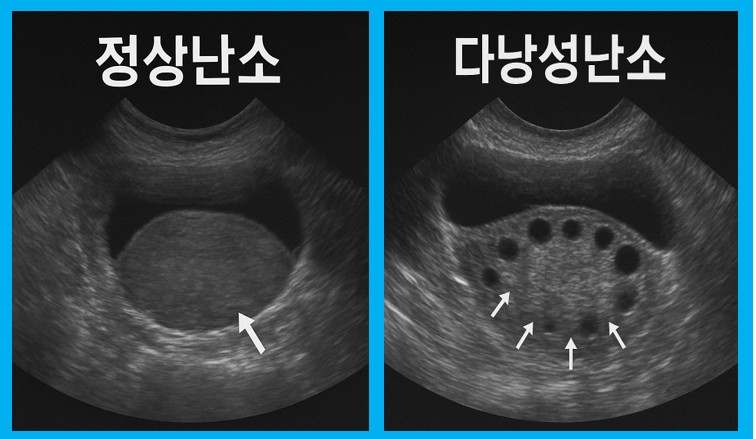

난소에 **여러 개의 미성숙 난포(물혹)**가 생기고 배란이 제대로 일어나지 않는 상태를 말합니다.

- 초음파상 난소에 12개 이상 난포 또는 난소 부피 증가